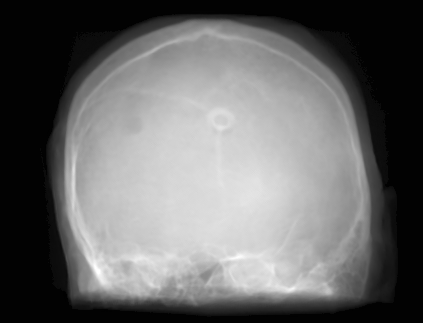

Figure 2: Inputs and outputs of the guided filtering pipeline based on the WDSR network. T1 & T2 MRI pairs (a)-(e) and CT & MRI projection images (f)-(j).

In Fig. 2 and 4, exemplary input, output and label images of the pipeline are presented for both tasks. Additional super-resolved images for both network architectures with and without the guided filter can be seen in Fig. 3. The results show a consistently high quality over both, the tomographic and the projective domain, as well as both tasks. Corresponding quantitative evaluation can be found in Table I and II. For SR, the WDSR network, i.e., the designated super resolution network, performs consistently better for both datasets with and without the guided filter. Applied to the tomographic images, the approaches without the guided filter deliver slightly better quantitative results. For the projection images this difference diminishes and both approaches are on par. In the case of denoising, the approaches with the guided filter deliver a lower mean absolute error while the structural similarity is increased without it. Though, the measurable differences are only marginal. The results generated by the plain guided filter without the learned guidance map are numerically worse than the approaches empowered by the guidance map generator for all tasks. This observation is most prevalent when observing the results of the tomographic T1 and T2 Flair images for SR, while for denoising the results are closer to the deep learning-based approaches.

In general, the decrease in image quality metrics w.r.t. to smaller radii is much stronger for the tomographic T1 and T2 Flair images than for the projection images. We assume the reason for this to be the difference in resolution of both datasets. The projection images resemble the ground truth more closely from the outset when compared to the tomographic images as seen in Fig. 2(b) and 2(g), respectively. Consequently, more information has to be generated by the networks. As the guided filter is sensitive towards correlation between the input and guidance map the constraints on the applicable changes are more severe.